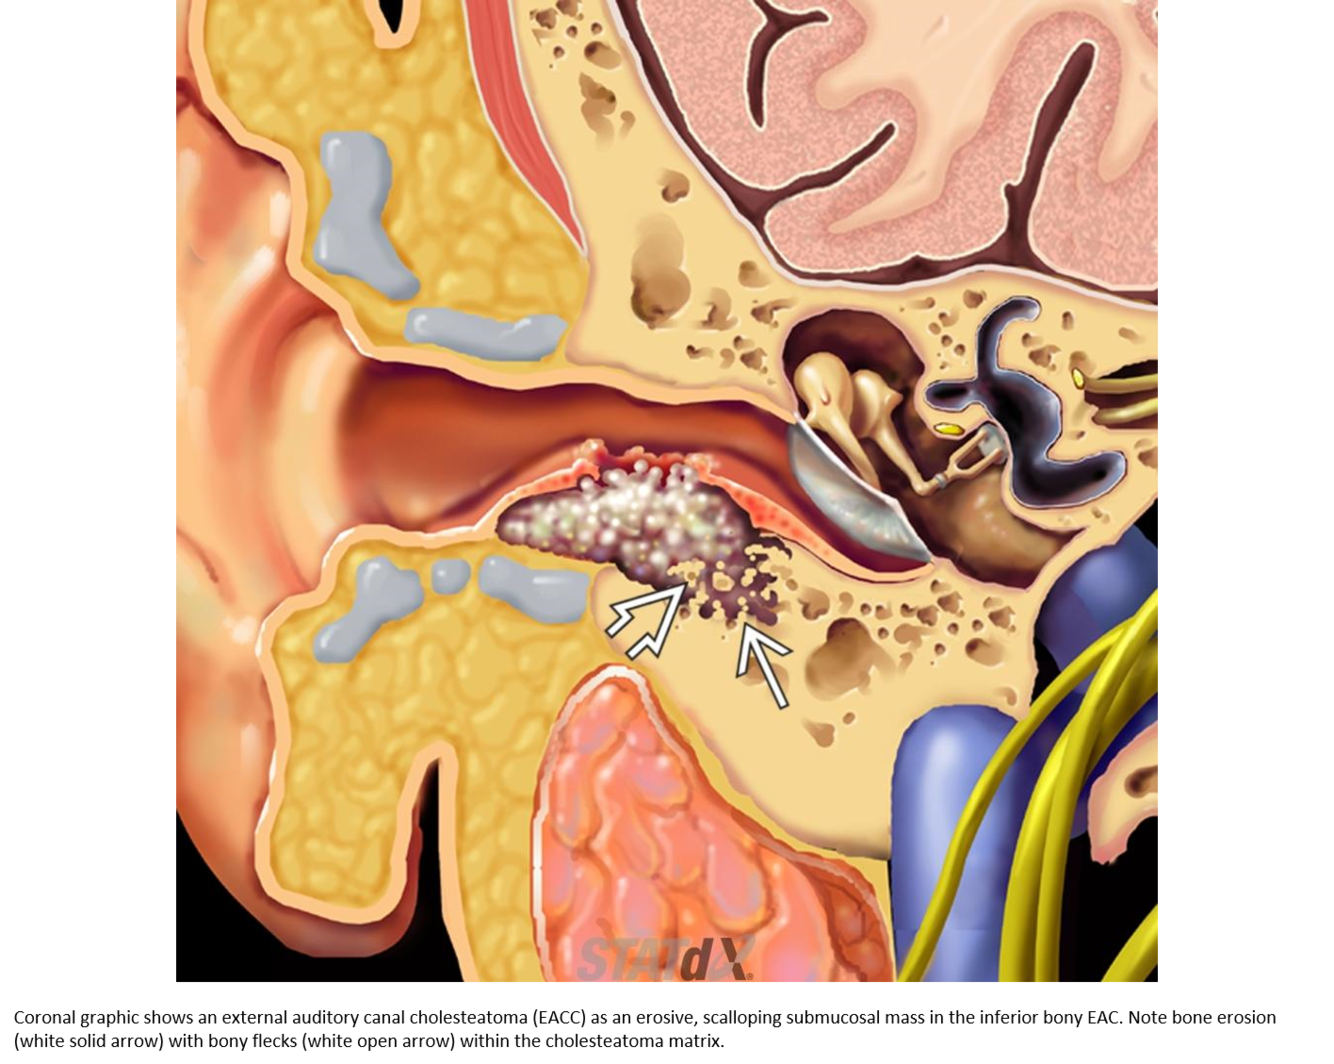

Medial epitympanic congenital cholesteatoma that erodes portions of the ossicles.

Solid arrow: choleastatoma

open arrow: erosion of the long process of the incus and hub of the stapes

Curved arrow: erosion of the lateral bony margin of the tympanic segment of the facial nerve canal

**Tympanic segment of the facial nerve will always be aberrant in the location of the oval window instead of inferior to the lateral semi-circular canal